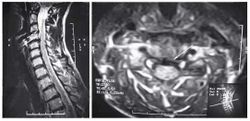

Пациентка С., 37лет, штукатур, заболела остро примерно 2 нед назад, когда утром после сна отметила острую боль при движении в шейном отделе позвоночника, ощущение скованности в шее, невозможность повернуть голову влево. В течение дня к болям в шейном отделе позвоночника постепенно присоединилась боль, иррадиирующая в левую лопатку, надплечье, по наружной поверхности левого плеча, которая имела жгучий и ломящий характер. Боль в руке и надплечье сохранялась в ночное время, нарушая сон, и частично уменьшалась в положении лежа с согнутой в локтевом суставе и заложенной за голову левой рукой. При наклоне головы в больную сторону пациентка эпизодически отмечала появление парестезий в виде «ползания мурашек» по наружной поверхности левого плеча. Прием НПВС и трамадола почти не приносил облегчения. В неврологическом статусе отмечено снижение болевой и температурной чувствительности в области левого надплечья и по наружной поверхности левого плеча, гипотония и снижение рефлекса с сухожилия двуглавой мышцы плеча слева, ограничение всех движений в шейном отделе позвоночника, но в большей степени - ротации и бокового сгибания влево. Наклон головы влево с аксиальным давлением на нее приводил к усилению боли в плече. Отмечено напряжение и умеренная болезненность при пальпации левой передней лестничной и трапециевидной мышц при отсутствии в них ТЗ. По данным рентгенографии шейного отдела позвоночника, выявлено снижение высоты межпозвоночных промежутков СIII-СIV СIV-СV, субхондральный остеосклероз, артроз дугоотростчатых суставов СIV-СV, унковертебральный неоартроз СIII-СIV СIV-СV Сагиттальный размер спинномозгового канала составил 16 мм. При МРТ шейного отдела позвоночника выявлена левосторонняя протрузия на уровне СIV-СV размером до 4,5 мм с компрессией дурального мешка, циркулярная протрузия на уровне СIII-СIV до 2 мм. Таким образом, при сопоставлении данных клинического обследования (невропатический характер болевого синдрома, наличие характерных для поражения корешка С5 чувствительных, двигательных и рефлекторных нарушений) с данными рентгенографии и МРТ позвоночника - наличие на соответствующем уровне (СIV-СV) латеральной протрузии и дистрофических изменений дугоотростчатого сустава с формированием сужения левого корешкового отверстия - у пациентки можно диагностировать компрессионную радикулопатию корешка СV слева, обусловленную левосторонней грыжей диска СIV-СV на фоне первично узкого спинномозгового канала на шейном уровне (Рис. 2). ЭМГ-обследование не проводили из-за небольшой (менее 3 нед) длительности заболевания и дальнейшей его положительной динамики на фоне лечения. Пациентке были назначены венотонические препараты (эскузан по 15 капель 3 раза в сутки), амитриптилин в дозе 50 мг/сут, внутривенные инфузии пентоксифиллина (5 мл 2% раствора), массаж мышц левой руки и надплечья, мануальная терапия (мобилизация шейных и грудных ПДС), ПИР трапециевидной и лестничной мышцы. На 10-е сутки лечения болевой синдром значительно уменьшился, его полный регресс произошел через 1,5 мес после начала заболевания.